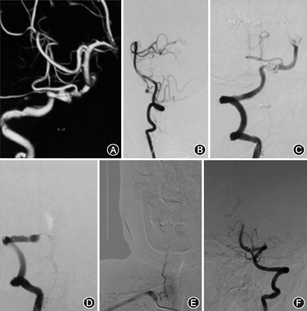

典型病例介绍:例1.患者女,55岁,因突发头痛12 h,加重伴恶心呕吐、意识丧失3 h入院,颅脑CT检查显示SAH,DSA检查显示PICA前型DAVA,行动脉瘤+载瘤动脉近端栓塞术,术后患者神志逐渐转清,言语正确,四肢活动正常,改良RANKIN量表(mRS)评分1分,见图1。例2.患者男,48岁,因突发头晕11 d入院,查体无明显阳性体征,颅脑CT检查未见颅内出血,DSA检查显示,PICA中型DAVA,行3层支架置入术,术后患者症状消失,神志清,言语正确,四肢活动正常,mRS评分0分,见图2。例3.患者男,70岁,因突发剧烈头痛伴恶心、呕吐8 d入院,颅脑CT检查显示SAH,DSA检查显示PICA后型DAVA,行支架辅助微弹簧圈栓塞术,术后患者病情稳定,神志清,言语正确,四肢活动正常,mRS评分0分,见图3。